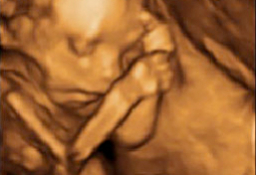

A lo largo del embarazo, el médico te recomendará una serie de pruebas diagnósticas para asegurarse que tu hijo se desarrolla correctamente, como la ecografía. Otras solo se prescriben cuando el ginecólogo sospecha que algo puede ir mal y necesita más datos para corraborarlo, como la amniocentesis o el control del bienestar fetal. Te contamos cómo y cuándo se realizan.